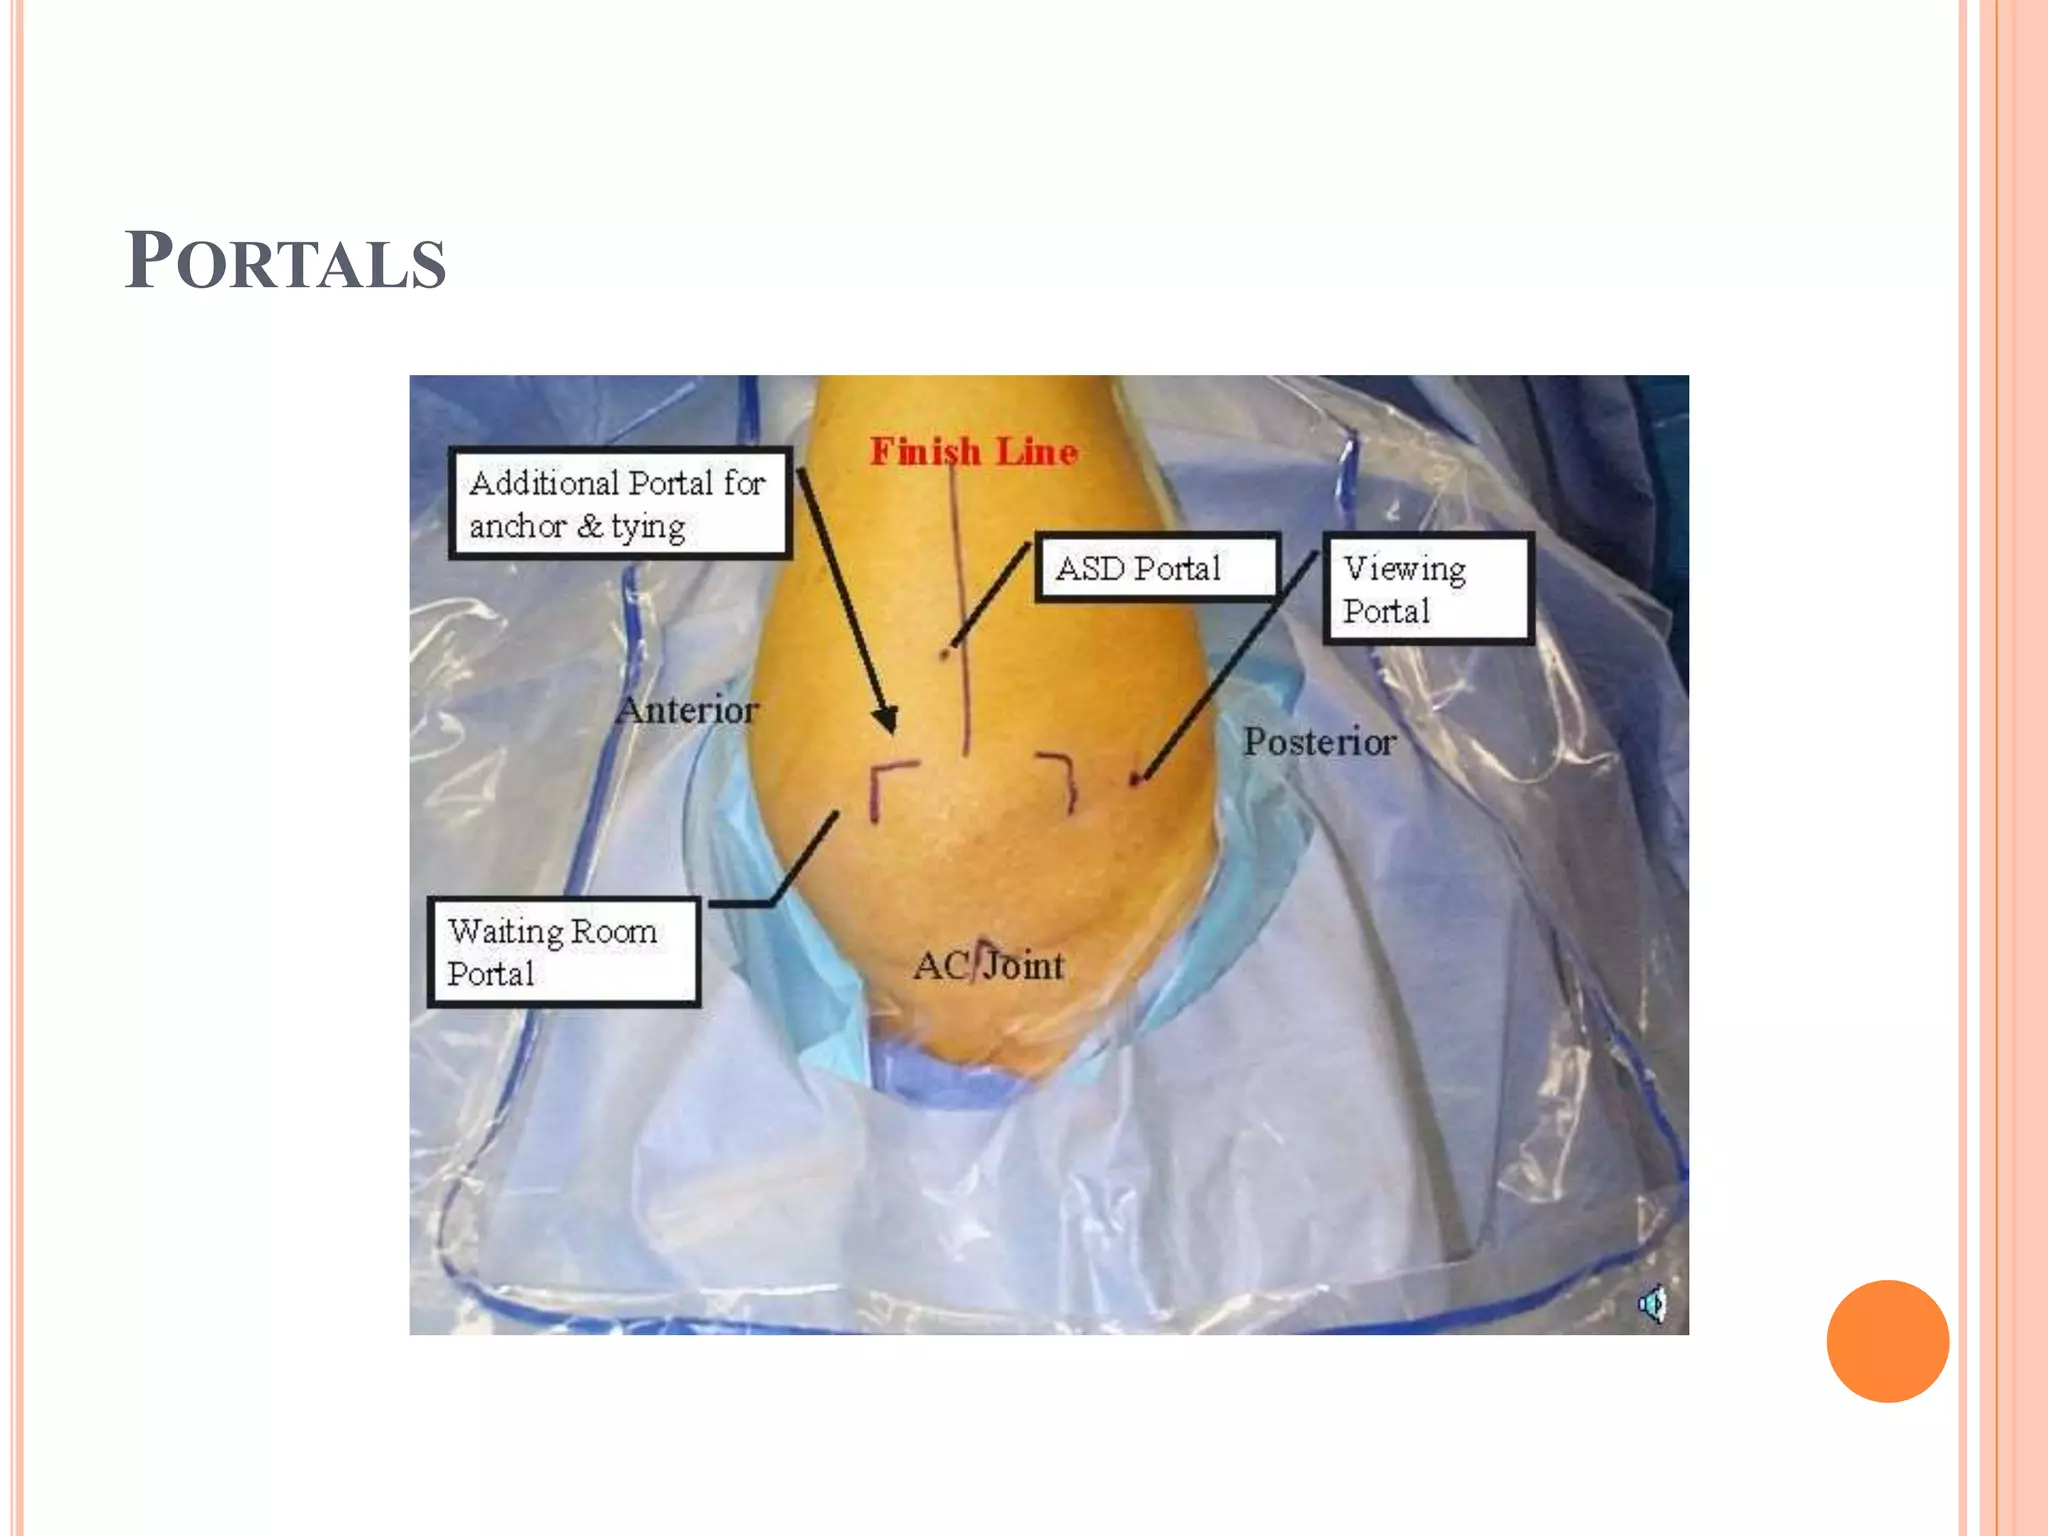

PORTALS

ANCHOR SUTURES